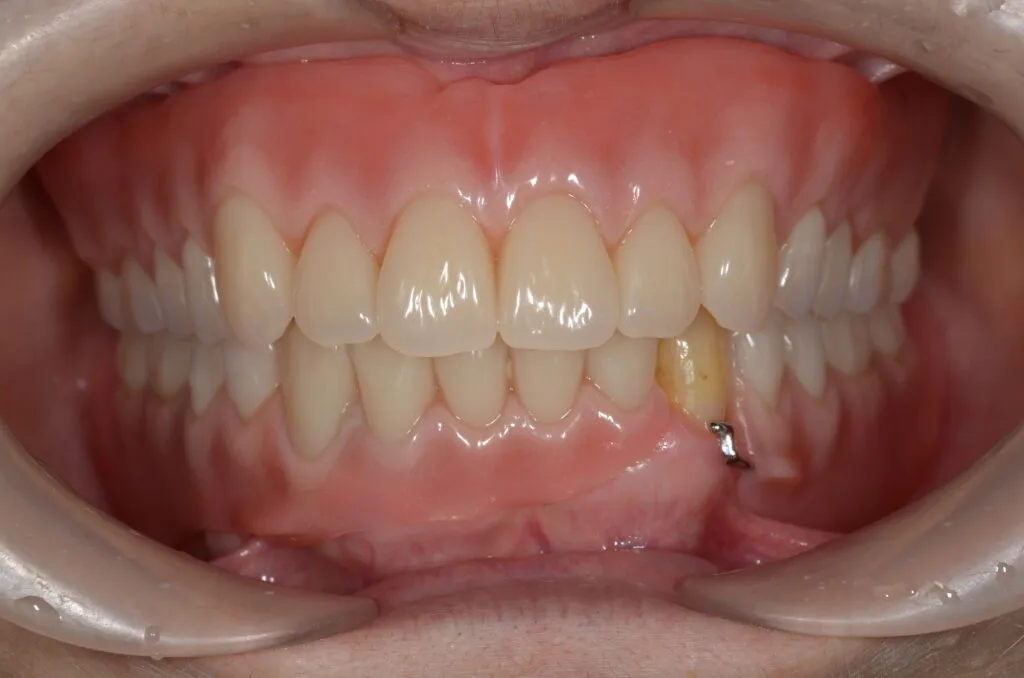

こちらの患者様の場合

【期間】2ヶ月

【費用】¥350,000~¥450,000/片顎(税抜)

【デメリット】精密に製作するため、保険の入れ歯よりも回数・費用がかかります。

上の写真は当院で上下総義歯を作製された患者さんです